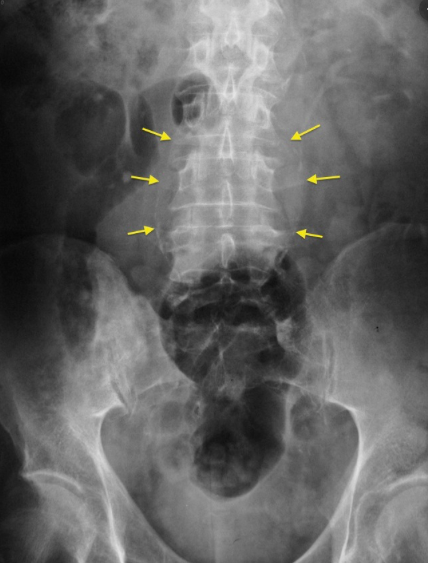

What is being shown on this abdominal x-ray?